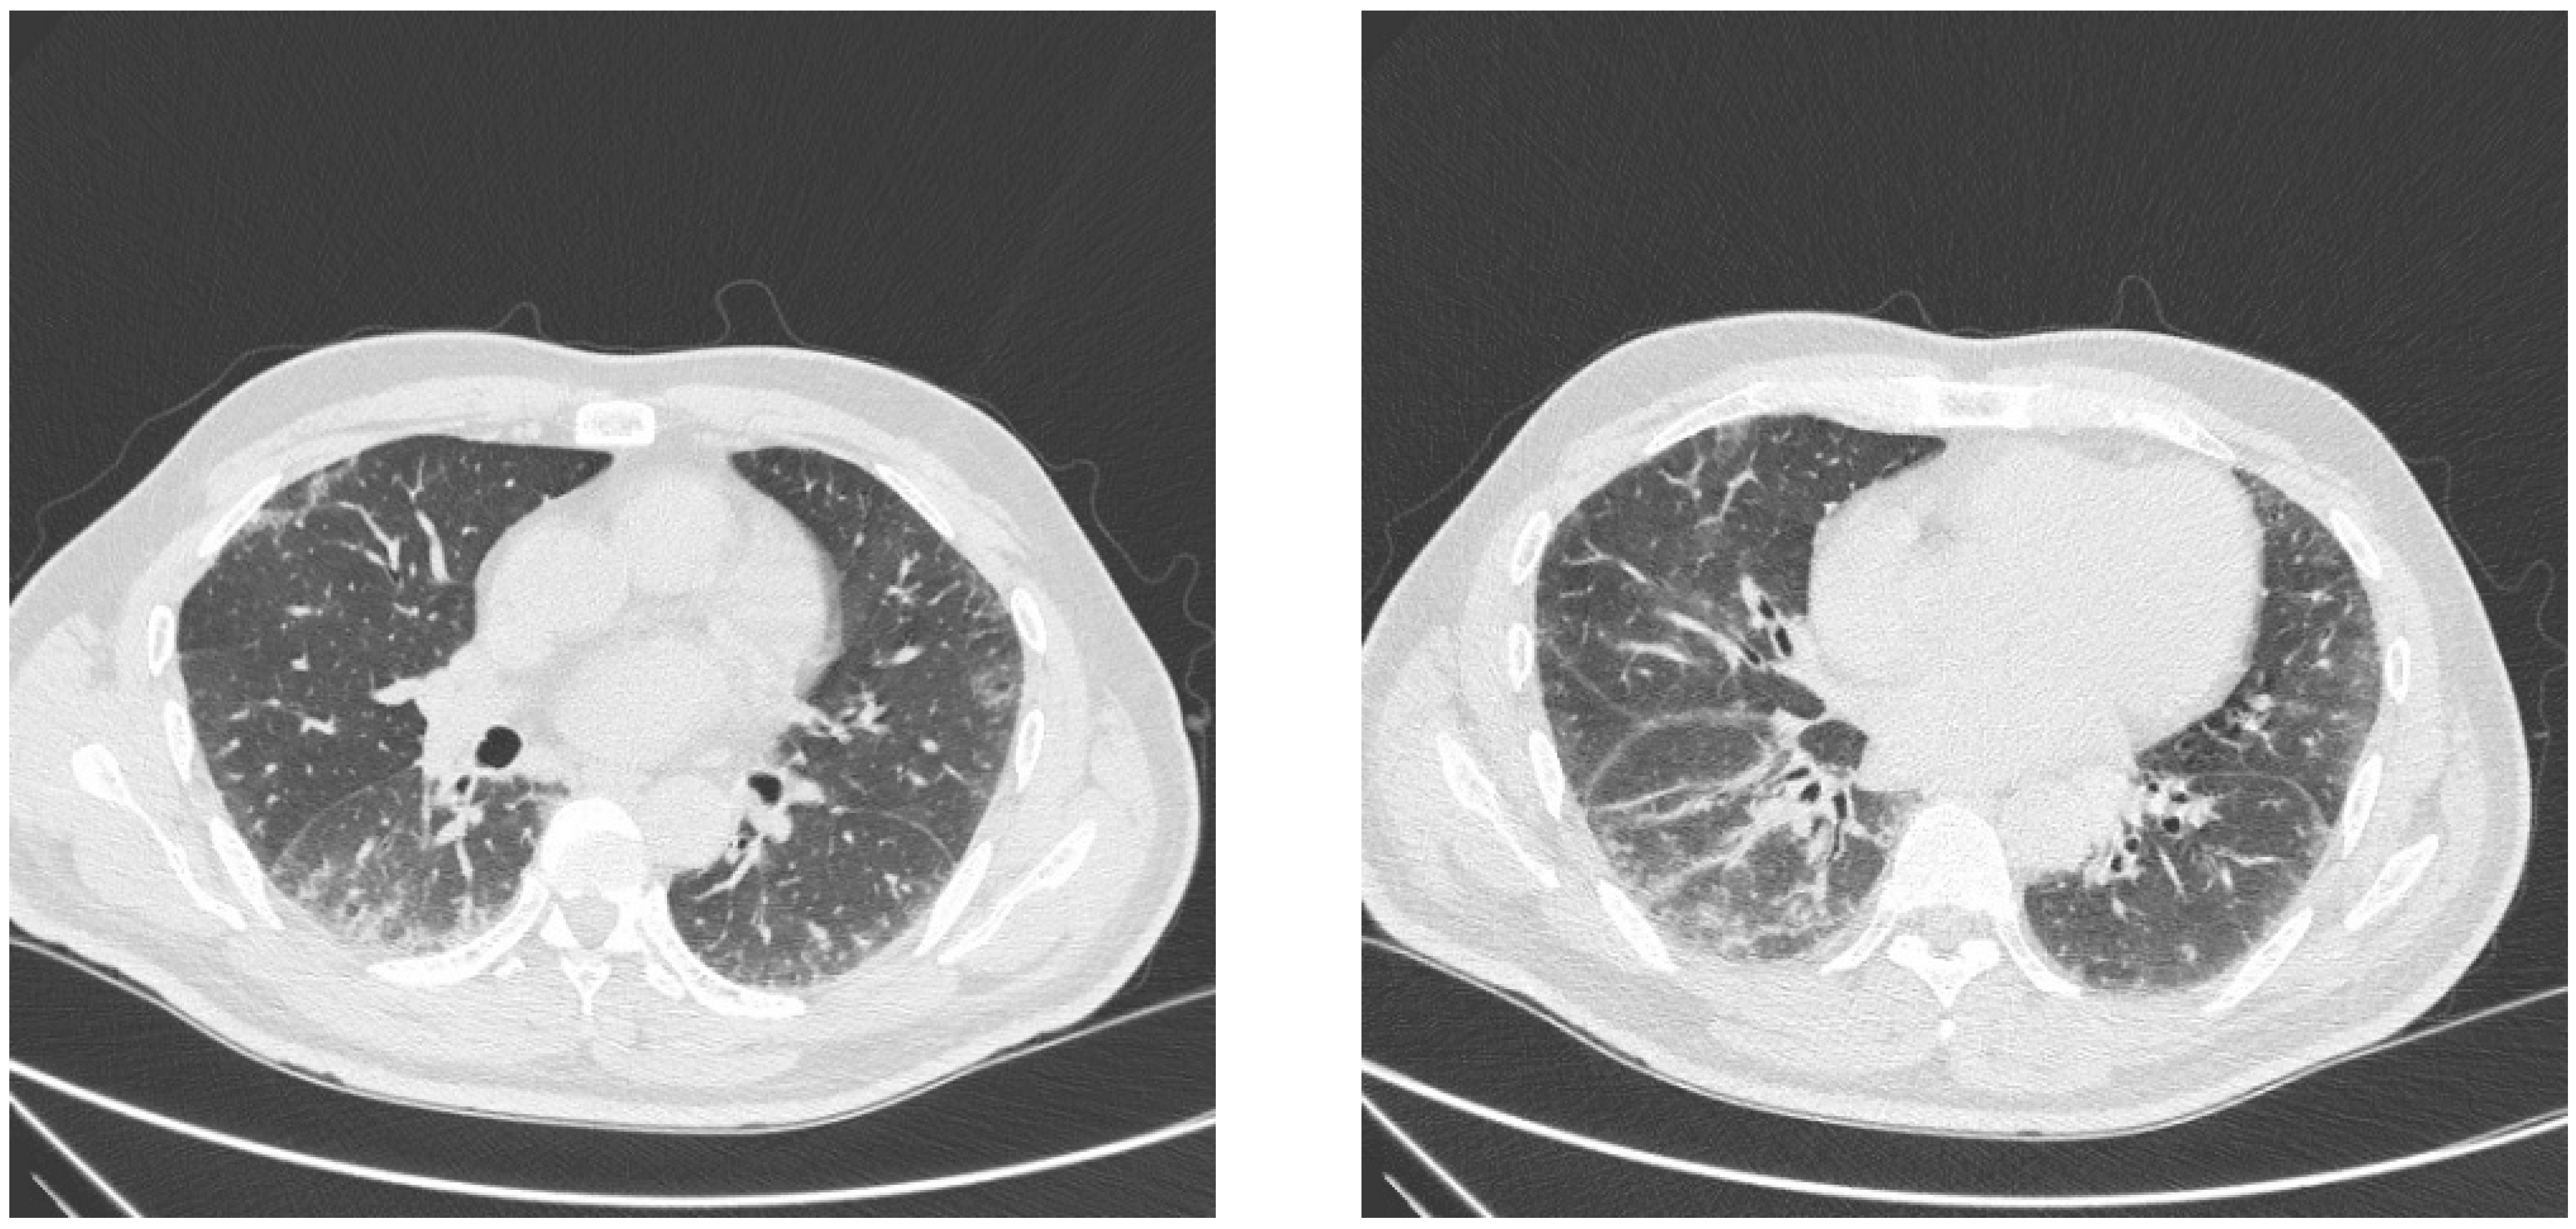

7. Imaging and Histology

- Waseda, Y.; Johkoh, T.; Egashira, R.; Sumikawa, H.; Saeki, K.; Watanabe, S.; Matsunuma, R.; Takato, H.; Ichikawa, Y.; Hamaguchi, Y.; et al. Antisynthetase syndrome: Pulmonary computed tomography findings of adult patients with antibodies to aminoacyl-tRNA synthetases. Eur. J. Radiol. 2016, 85, 1421–1426. [Google Scholar] [CrossRef]

- Debray, M.P.; Borie, R.; Revel, M.P.; Naccache, J.M.; Khalil, A.; Toper, C.; Israel-Biet, D.; Estellat, C.; Brillet, P.Y. Interstitial lung disease in anti-synthetase syndrome: Initial and follow-up CT findings. Eur. J. Radiol. 2015, 84, 516–523. [Google Scholar] [CrossRef]